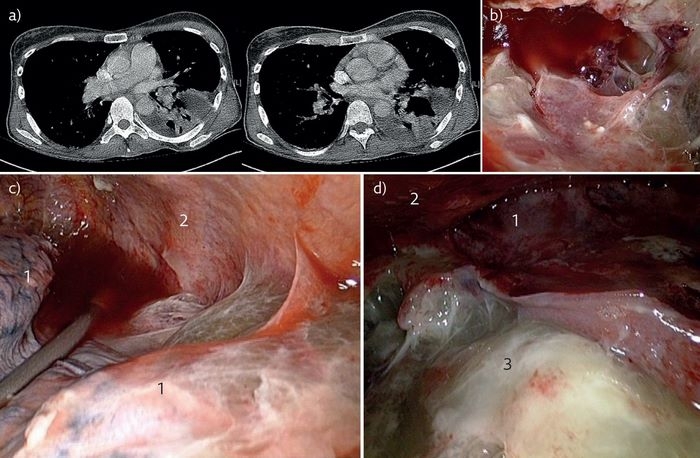

برای تشخیص، کشت چرک و نیز عکسبرداری از قفسه سینه با اشعه ایکس انجام میگیرد. درمان معمولاً شامل جراحی برای باز کردن حفره عفونی شده و تخلیه چرک است. این روش توراکوسنتز نامیده میشود. سیگار نکشید.